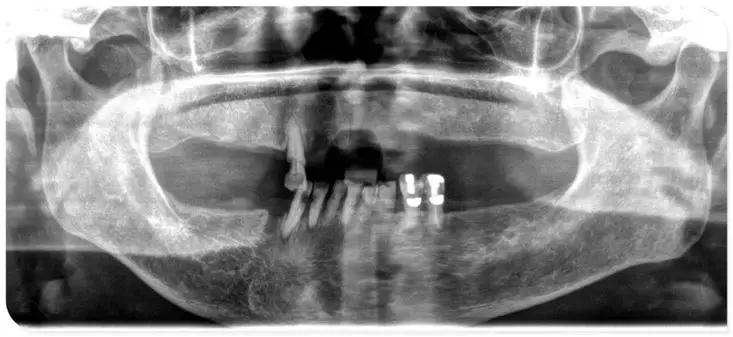

说实话,我妈的牙齿情况太差了,我们也没抱太大希望,医生建议我妈先去做个牙齿全景X光检查,经过拍片检查,医生当时诊断我妈口内的5颗松牙不用拔,可以重新做固定,牙根也是健康的能保留,可以直接在自己的牙根上镶牙,既稳固吃饭也更香,缺牙的部分采用无挂钩附着体技术修复。这样既缩短了治疗时间,又节省了费用。

这是我妈当时拍片的情况,牙都歪七八扭的